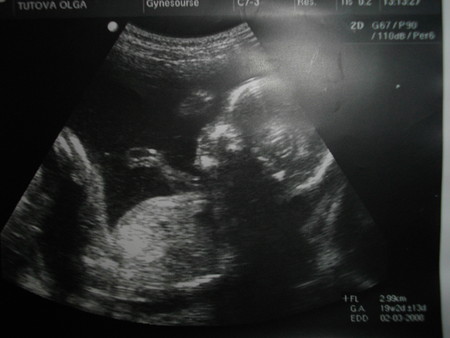

Тут нам 3 месяца